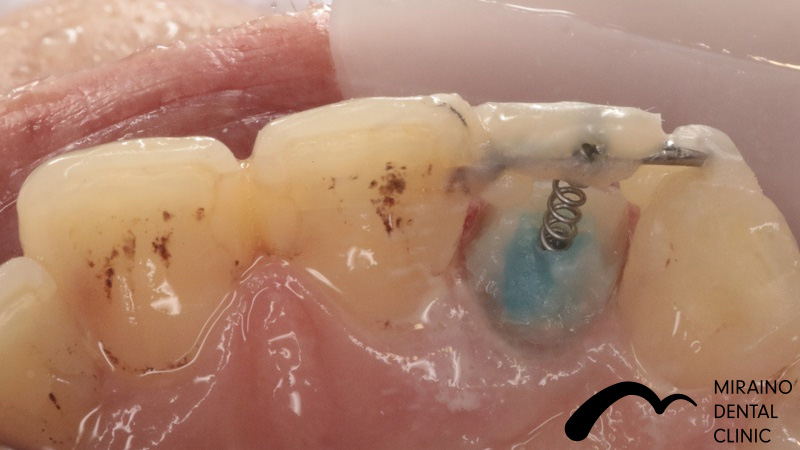

| 施術名 | 歯の破折予防:MTM |

| 施術の概要 | 前歯の差し歯の色が気になるということで来院されました。 噛んだ時に下の前歯が隠れており、治療した歯をより劣化させやすい噛み合わせ[過蓋伵合]の方でした。 歯を失う原因のうち、ムシ歯・歯周病以外に歯への負担荷重お伝えしましたが、 根本的な噛み合わせの治療は希望されなかったため、 次回再発した際は抜歯となる可能性が高いため、なるべく再発しにくい歯科治療を希望され、 MTMを行ったのちメタルフリークラウンでの歯冠修復行いました。 |

| 施術の内容 | ムシ歯や歯が折れておりで感染除去後に健康な歯が歯茎の下まで達する場合は、 通常、抜歯もしくは2年以内の抜歯前提の延命治療になってしまいます。 両サイドの歯に表装置をつけ骨からひっぱり出すことで、 歯根破折・歯冠脱離による抜歯の可能性を回避します。 部分矯正MTM(Minor Tooth Movement)の略で、 このような場合エクストルージョン(伾出)と言います。 |

| 1歯あたりの治療費 | 1歯につき50,000円 |